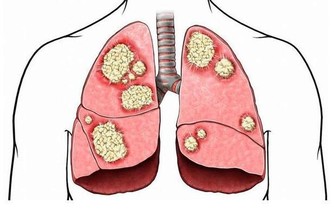

內因上,最多見的還是因心血管問題引起的心源性猝死,佔猝死事件的80%以上,包括冠心病、心肌病、遺傳性心律失常、病毒性心肌炎等。而以下三種便是最常見的內部因素——

*****2、病毒侵犯心臟****

即便是身體健壯,若是出現流行性感冒或者是病毒性腹瀉,那麼就要當心了,因為這一部分患者中約有4%的人會被病毒侵犯心臟。如果還連續熬夜,過度疲勞,免疫力還會下降,就更容易被病毒侵犯。

一旦病毒侵犯心臟傳導系統,那麼可會引起嚴重心律失常,嚴重的甚至室顫,最終猝死。